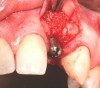

Fig 1. Case 1: A horizontal releasing incision across the edentate ridge at the site of tooth No. 8. It terminates 1 mm from the adjacent teeth.

Figure 1

In the esthetic zone it is preferable to avoid elevating papillae because flap elevation may induce recession and create unesthetic black triangles.4 If a flap is necessary to perform a procedure in an edentate area when adjacent teeth are present, the following technique can be used to circumvent blunting papillae. Make a horizontal incision along the midcrestal or palatal aspect of the ridge and terminate the incision 1 mm from the adjacent teeth (Figure 1). The incision is created palatally if it is desired to transpose keratinized tissue to the buccal. From the horizontal incision, create bilateral buccal vertical releasing incisions that extend obliquely at an angle (Figure 2). The vertical incisions can also be extended palatally (for access), but this is not always necessary (Figure 3). Preserved papillae contain gingival supracrestal fibers that subsequently help maintain papillary height (Figure 4). The distance the incision is extended vertically on the buccal is dictated by the task to be accomplished (eg, implant insertion only requires short vertical incisions, while bone grafting needs longer incisions) (Figure 5 and Figure 6). At the end of the surgical procedure, the severed papillary segments are sutured to their retained counterparts (Figure 7 and Figure 8). Figure 1 through Figure 8 demonstrate a submerged implant protocol.

In Figure 1 through Figure 8, tooth No. 8 is missing. If abundant bone and keratinized tissue is present, a punch procedure (flapless) can be used to access bone to place an implant. However, a flap should be elevated if there is a lack of keratinized tissue or if bone grafting or soft-tissue repair is required. There are two available options with respect to raising a flap: elevate it and include the papillae, or use papillae-sparing incisions. Each procedure provides advantages and disadvantages.